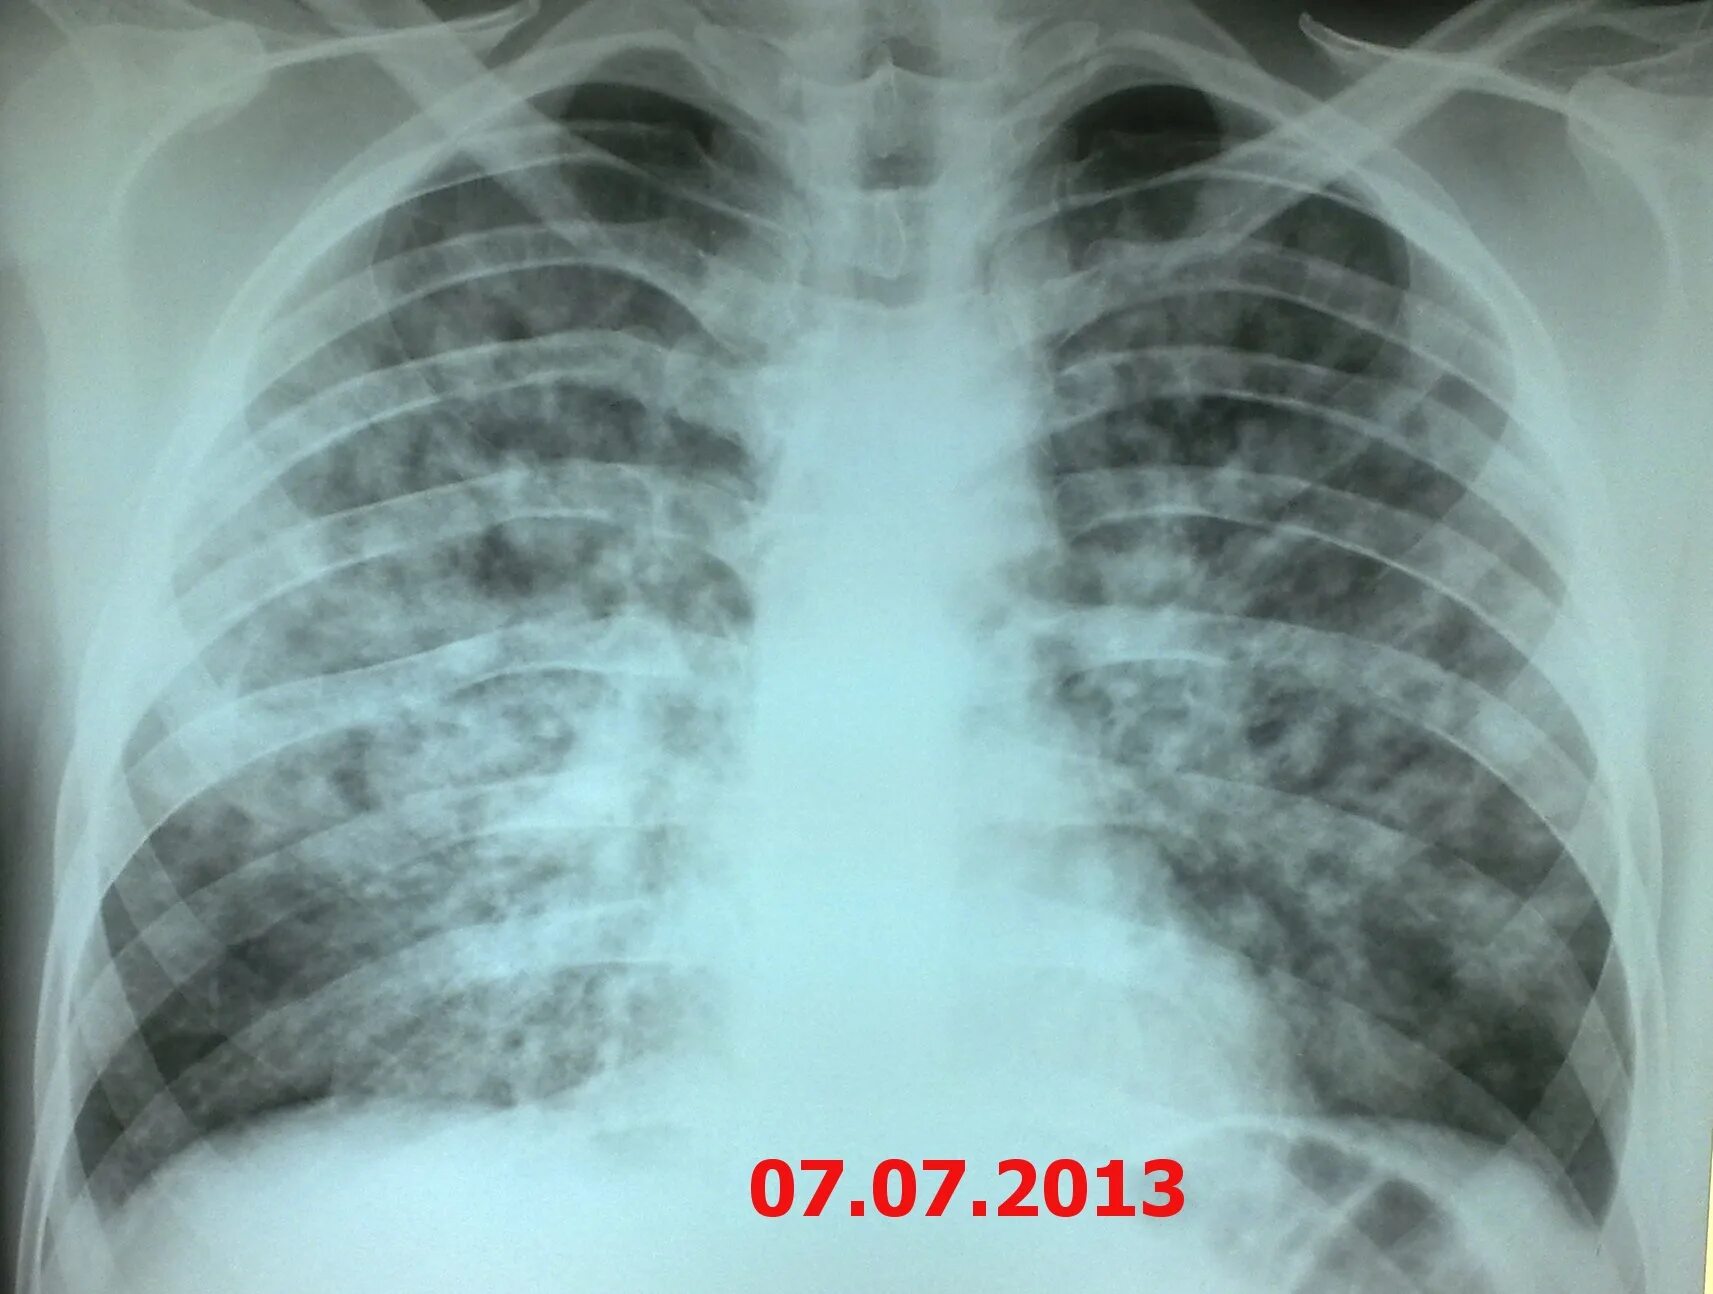

Диссеминированный туберкулез фаза инфильтрации